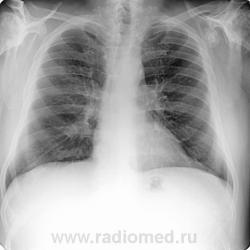

Пациент 60 лет, при прохождении проверочной флюорографии  обнаружены изменения со сторны плечевых суставов.Водитель троллейбуса.Страдает избыточной массой тела, люмбальгией, артороз коленных суставов.Непосредственно жалобы на плечевые суставы в медицинских документах не отражены. Какое будет мнение у коллег?

Пациент жалоб со сторны плечевых суставов не предъяляет и не помнит что бы когда- то что то беспокоило.Данных за сирингомиелию нет.

Александр, конечно надо доснять плечевые суставы... Из того, что есть: видимые отделы плечевых костей выглядят довольно симметрично, хотя слева и похуже, думаю - артроз. Весьма настораживает левая лопатка на предмет хондросаркомы

Уважаемый Александр, приходиться признать, что на цифровой рентгенограмме легких изменения плечевых суставов видны лучше, чем на "обрезаных" и недоэкспонированых снимках суставов. По имеющимся данным могу только сказать, что деф. артроз с кистовидной перестройкой структуры есть. Под хрящевой опухолью (возможно - хондросаркома) левой лопатки я имела в виду тень, отмеченую красными стрелками, которая в поле снимка не вошла. Моя вина - в силу специфики работы такие узкоформатные снимки давно были вредными, т.к. очень часто патология остается за пределами снимка. Остается рекомендовать рентгенография левой лопатки в прямой передне-задней и косой проекциях, а лучше - КТ...